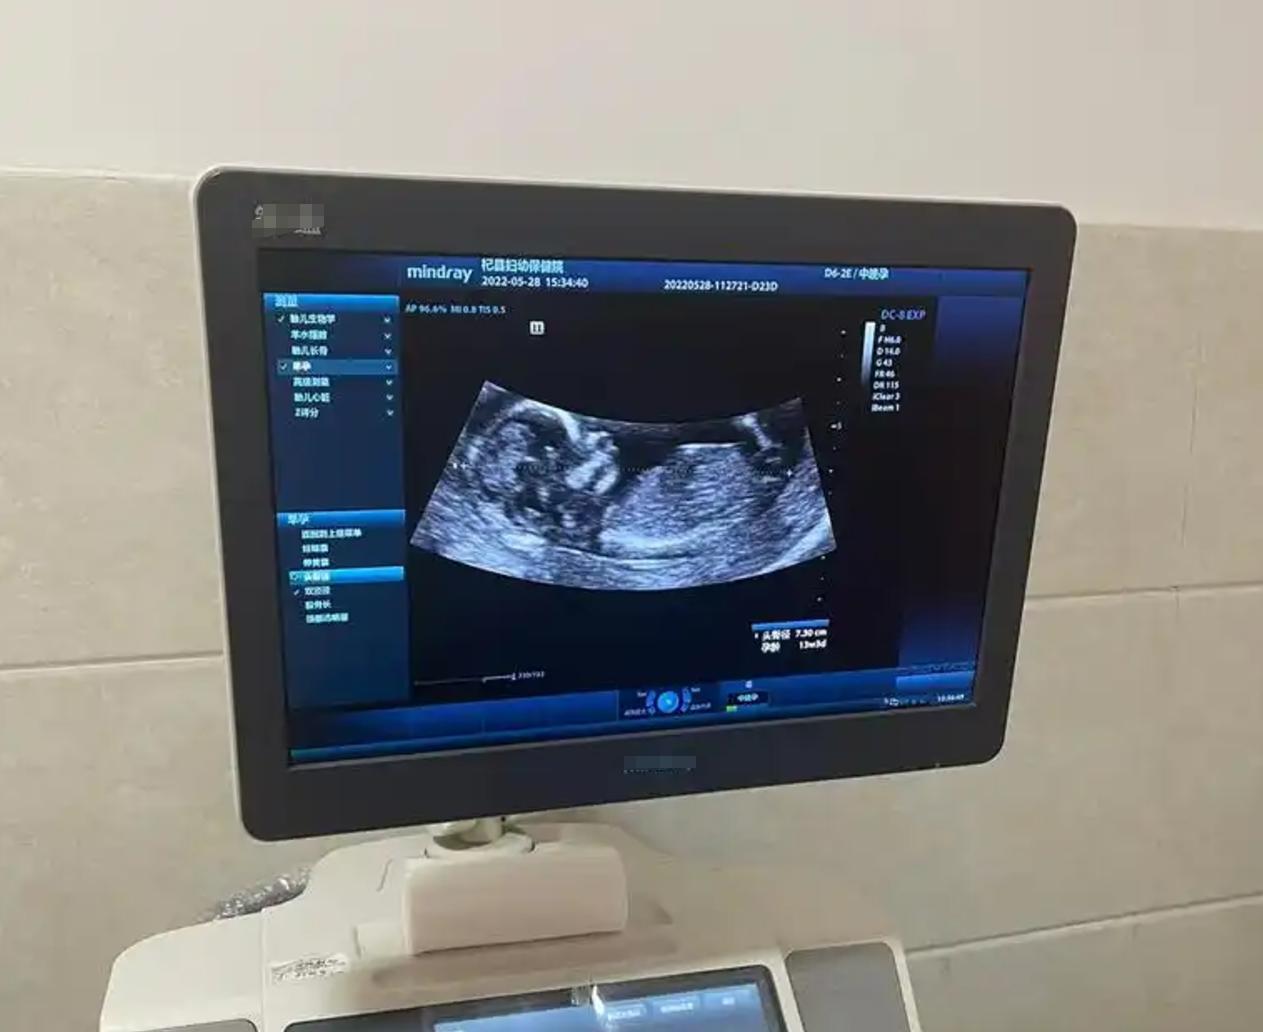

在懷孕22周照B超的時候,醫生一邊做檢查一邊皺着眉頭,然後就問小青:你老公有多高啊?小青說:我老公沒多高,1米63吧!醫生聽了之後就沒吭聲了,後來就跟她說孩子沒啥問題,你把檢查結果拿去給產檢醫生看吧!

而小青拿着自己的B超結果去給產檢醫生看的時候,產檢醫生看了一看也問她:你老公多高?小青也覺得很納悶,爲什麼兩個醫生都問我老公的身高呢?於是又回了一句:1米63。產檢醫生又不吭聲了。

小青這時候就忍不住了,孩子是不是有啥問題呀?爲啥要問爸爸的身高?因爲現在產檢的產婦比較少了,所以產檢醫生的時間也沒有那麼緊,產檢醫生也比較和藹。於是就跟小青說:你這個孩子現在孕22周了,正常情況下他的股骨長應該有3.8釐米左右,但是現在這個孩子的股骨長只有3.6釐米,相當於這個孩子的股骨長足足少了一週。

我看你身高也有1米6,在女生中也不算矮,所以就要了解一下他爸爸的身高,如果爸爸長得高的話,孩子的股骨長還要短的話,那就要引起警惕,現在看來孩子可能是遺傳到爸爸,所以股骨長不會很高。但是現在很多孩子雖然父母不高,以後也可能長高的,孩子出生之後多注意營養,多注意運動就可以了。